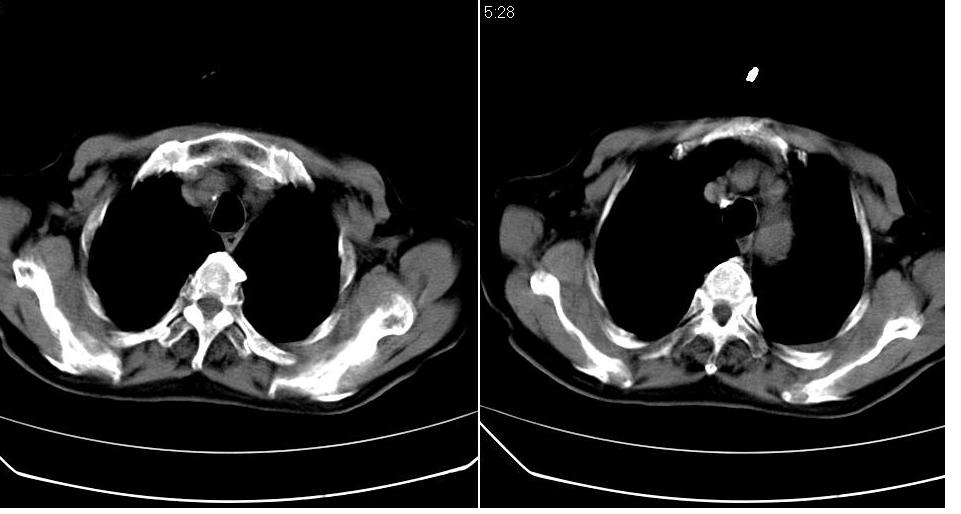

男 80岁,外院病人,有脑梗塞病史,近两个月发热,体温38.5度左右,抗炎后体温正常,药物停有发热。

左肺下叶略萎陷、实变,内可见含气支气管征。左舌叶、中叶亦见少许斑片状高密度区,边界不清。纵隔未见肿大淋巴结影。

考虑:1、肺感染;

2、建议严格抗炎治疗后复查。

左下肺体积缩小,密度增高,见片增密影。边界模糊,见支气管充气像,肺门纵隔无异示,心脏气管左移,左侧胸腔少量积液。考虑肺部感染伴部分肺不张[有脑梗塞病史坠积性肺炎可能]